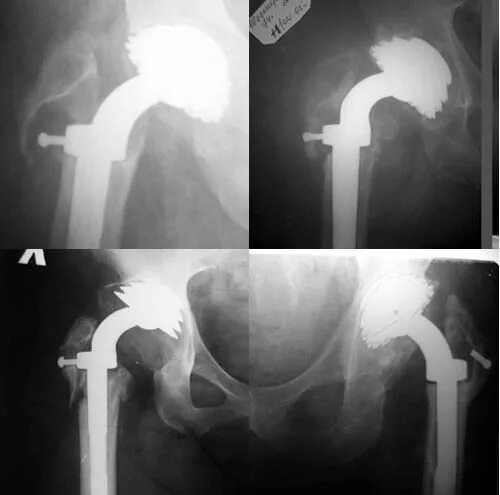

Ревизия тазобедренного сустава